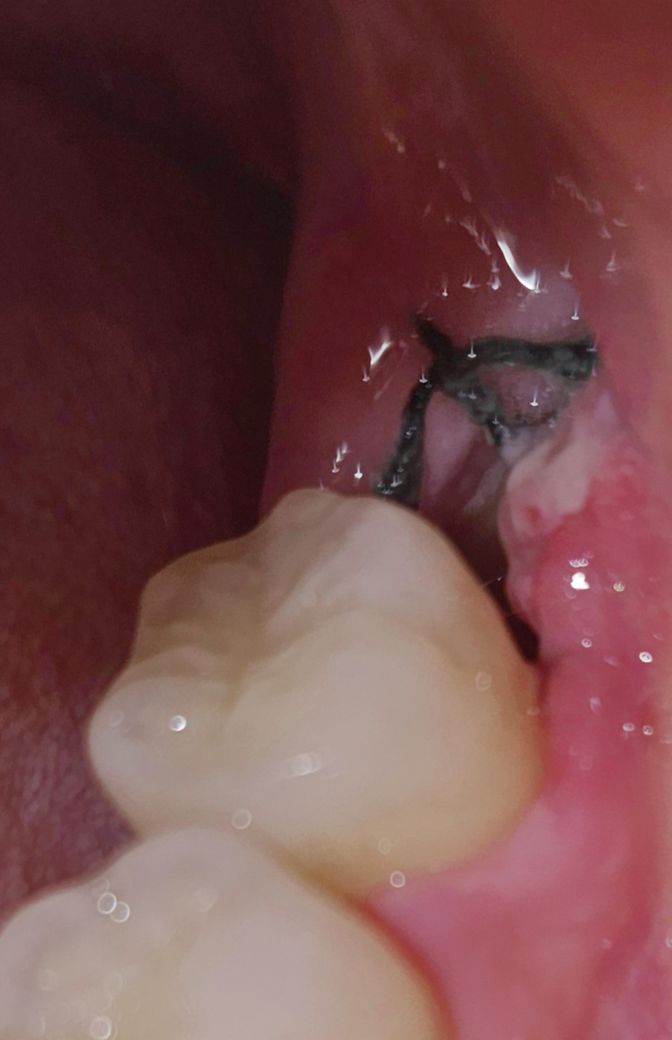

발치한지 5일 차인 오늘 촬영한

해당 부위의 사진들을 보시고

드라이소켓(건성발치와)인지 한번 봐주신다면

감사하겠습니다.

• 1번 째 사진